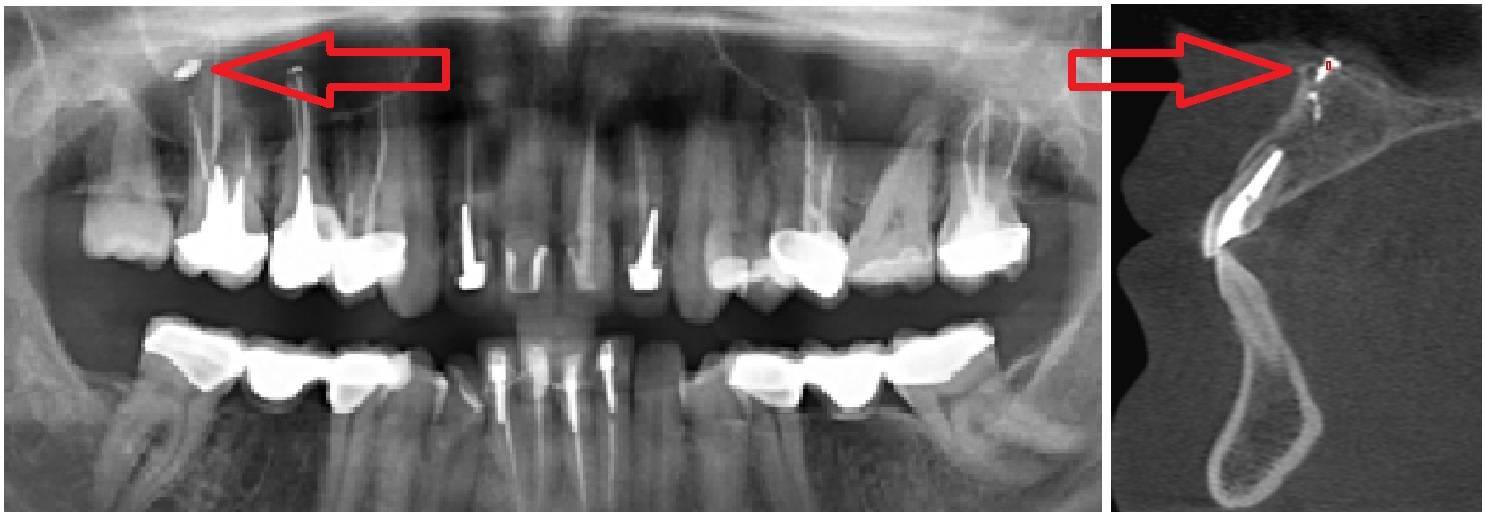

Выведение материала при пломбировании корневых каналов в носовую пазуху.

Стоматолог может использовать специальные инструменты и техники для удаления материала, такие как ультразвуковые аппараты или микроскопы.

В некоторых случаях может потребоваться хирургическое вмешательство для удаления пломбировочного материала.

Осложнения при лечении пульпита. Попадание пломбировочного материала за пределы корня зуба

Пломбировочный материал в Гайморовой пазухе и что с этим делать. В конце готовлю плов ))))